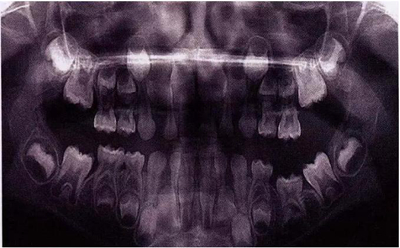

文獻直達|乳磨牙下沉的臨床管理

圖1:輕度下沉的臨床像

臨床檢查看到合平面出現(xiàn)擾動可做為診斷依據(jù)。下沉乳磨牙位于合平面的凸起端(圖4)。這些牙齒在使用金屬器具敲擊時,會發(fā)出典型的高調(diào),固連“有裂紋茶杯”聲。同時還需要做影像學檢查,以確認繼承恒磨牙是否缺失。

X線片還會顯示合平面呈現(xiàn)出一個臺階,并通常會有一個角度朝向固連牙的角型牙槽骨缺損。(圖5)。許多臨床醫(yī)生更愿意選擇拍攝曲面體層片而不是根尖片,因為考慮到乳牙下沉經(jīng)常會雙側(cè)發(fā)生并合并其它發(fā)育異常,同時也為了確定是否需要正畸治療。臨床檢查和影像學檢查聯(lián)合評估同樣也為了排除其它病因,譬如原發(fā)性的萌出障礙,牙齒嵌入或者其它異常。